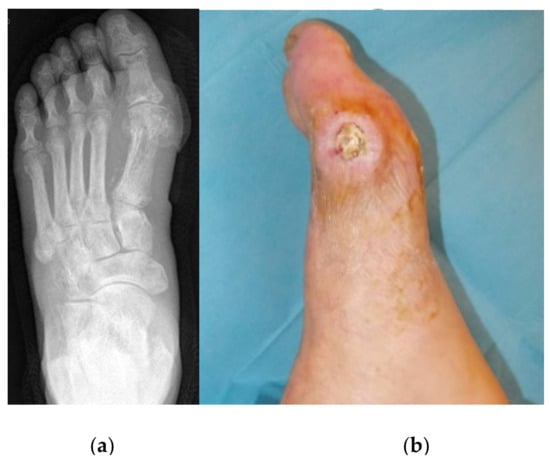

3.2. Metatarsal Lesions